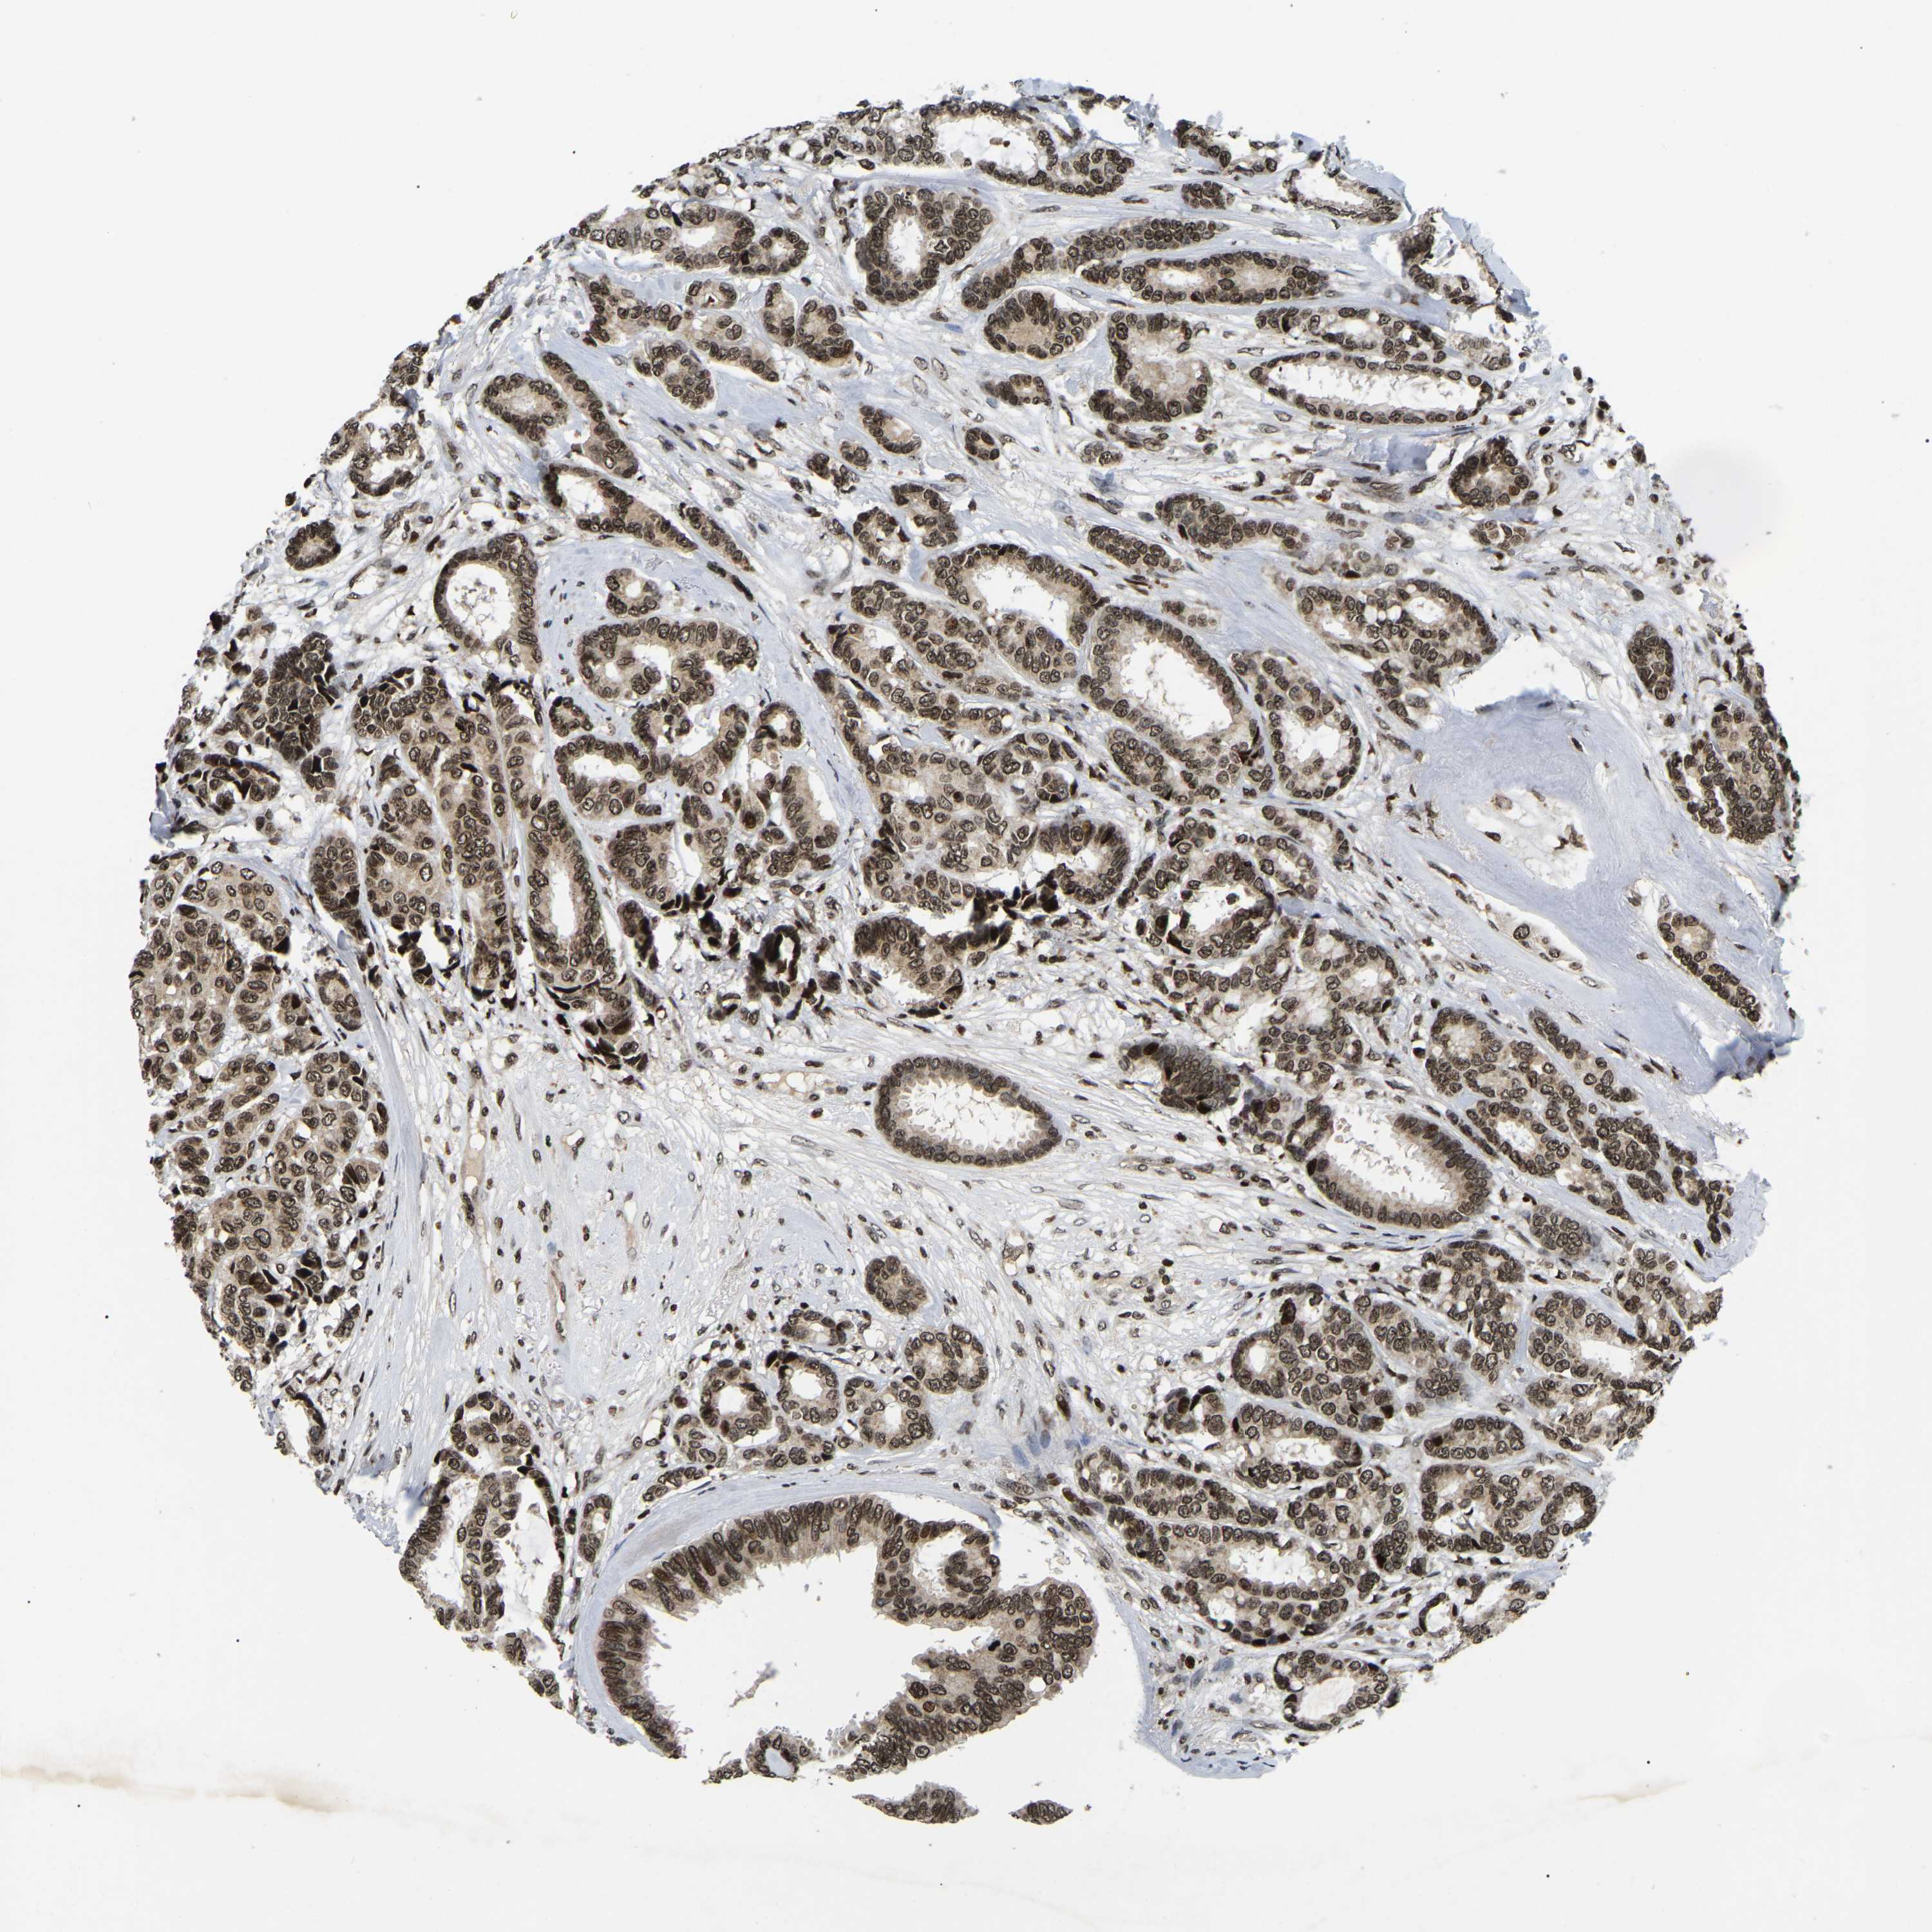

BRCA TCGA BRCA VALIDATION PROTEIN EXPRESSION

ANTIBODIES

AND

VALIDATION